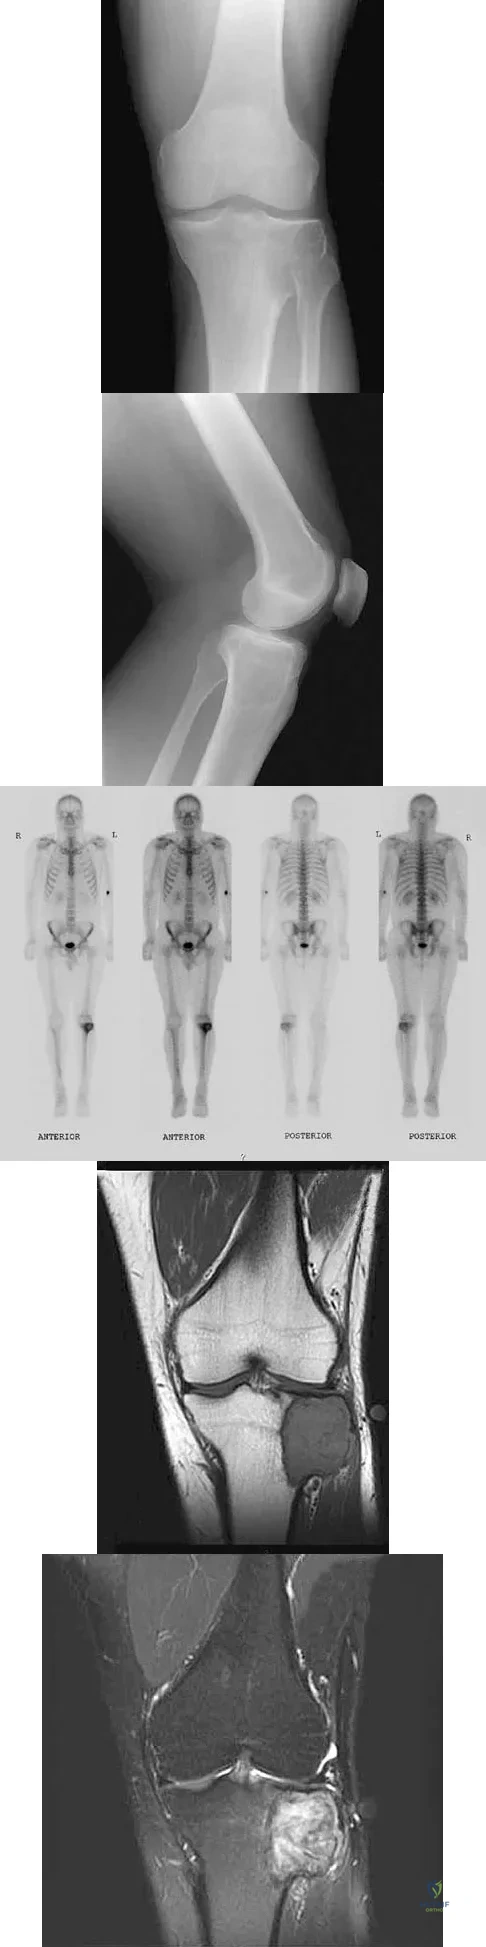

A 24-year-old man has had pain in the left knee for the past several months. He reports that initially the pain was associated with weight-bearing activities, but it has now become more constant. He denies any swelling but reports a lateral fullness at the tibial plateau. Figures 23a through 23e show radiographs, a bone scan, and T1- and T2-weighted MRI scans. What is the most likely diagnosis?

Explanation